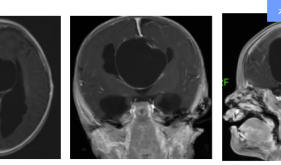

神经外科三区是医院成立较为年轻的科室之一,是茂名市临床重点专科(神经外科)的亚专科病区,以神经系统肿瘤的个体化综合治疗为专业特点。目前,专科柔性引进了周向阳博士担任神经外科三区科室主任,并汇集了一支高素质、专业化的医疗团队,致力于为患者提供全面、精准的神经系统疾病诊疗服务,同时以先进的治疗理念和技术手段为特色,不断引进和创新诊疗方法,为患者提供更加安全、有效的治疗方案。神经外科三区致力于以神经内镜技术(微侵...